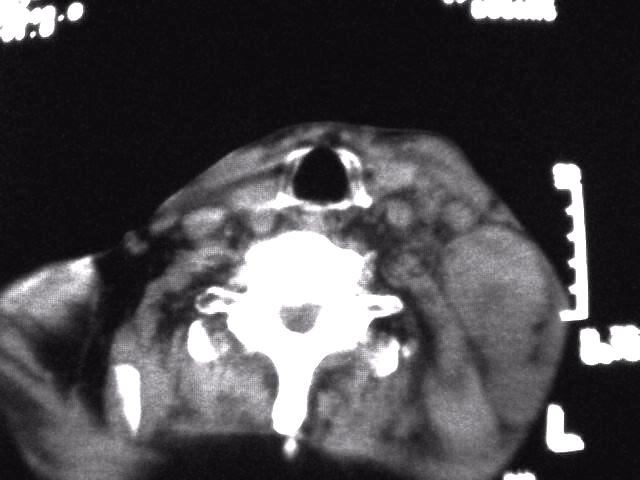

颈部层厚10mm间距10mm连续扫描及增强扫描共24层示:左侧下颈部胸锁乳突肌内侧区域内可见多发软组织结节,密度不均,内可见斑片状低密度区,大小不等,部分融合成块,左侧融合成一块者大约9.0x5.4,与周围肌肉、血管等结构界面不清,骨质未见明显浸润影。左侧锁骨下可见多个软组织结节,与周围界限尚清,左侧锁骨上窝内可见一大软组织肿物,大小约4.7x3.7cm,内密度欠均匀中心可见低密度区。

考虑:左侧颈部及双侧锁骨下多发淋巴结肿。非何杰金氏淋巴瘤可能性大,建议进一步检查。